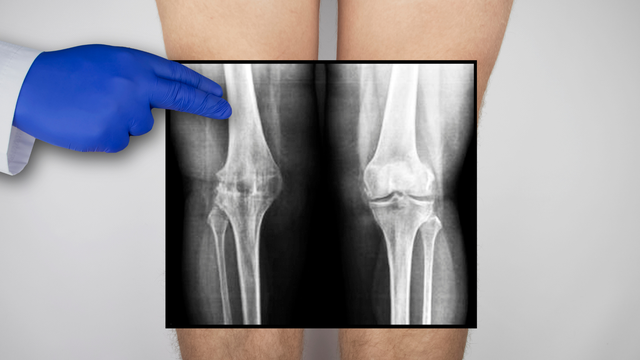

:format(webp)/mri_dut_day_chang_cheo_truoc_2_d8b5e23621.png)

Dây chằng chéo trước (ACL) là một trong những cấu trúc quan trọng của khớp gối, giúp ổn định và kiểm soát chuyển động. Khi bị chấn thương đứt dây chằng chéo trước có thể gây đau đớn và ảnh hưởng nghiêm trọng đến khả năng vận động. MRI đứt dây chằng chéo trước là phương pháp chẩn đoán hình ảnh tiên tiến, giúp đánh giá chính xác mức độ tổn thương của dây chằng chéo trước mà không cần can thiệp xâm lấn phục vụ chẩn đoán và theo dõi điều trị các vấn đề liên quan.